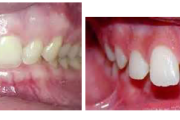

Puudub ülemine tsentraalne intsisiiv, kuid külgmised lõikehambad on juba lõikunud.

Turritavad ülemised lõikehambad.

Puudub ülemine tsentraalne intsisiiv